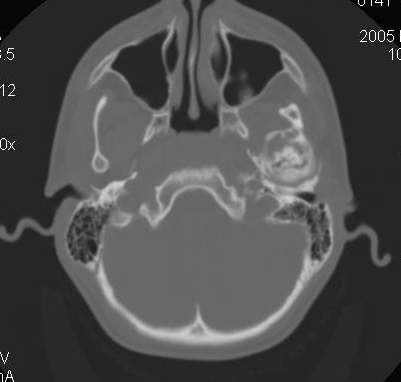

Пациент В., 13 лет. Диагноз: Костный анкилоз левого височно-нижнечелюстного сустава (ВНЧС), левосторонняя микрогения. Болеет с 2-х летнего возраста. Возможная причина развития анкилоза – воспалительный процесс (в первые 1,5 года жизни часто болел простудными заболеваниями, травму родители отрицают). В 3 и 5 лет проводилась редрессация – безуспешно. Прилагаются: ортопантомограмма, кадры СКТ с 3Д реконструкцией. Вопросы: определение тактики лечения – вид и сроки реконструктивно-пластической операции (этапов операции), а именно – неоартропластики и устранения микрогении, медикаментозная терапия в до- и послеоперационный период, ортодонтическое лечение.